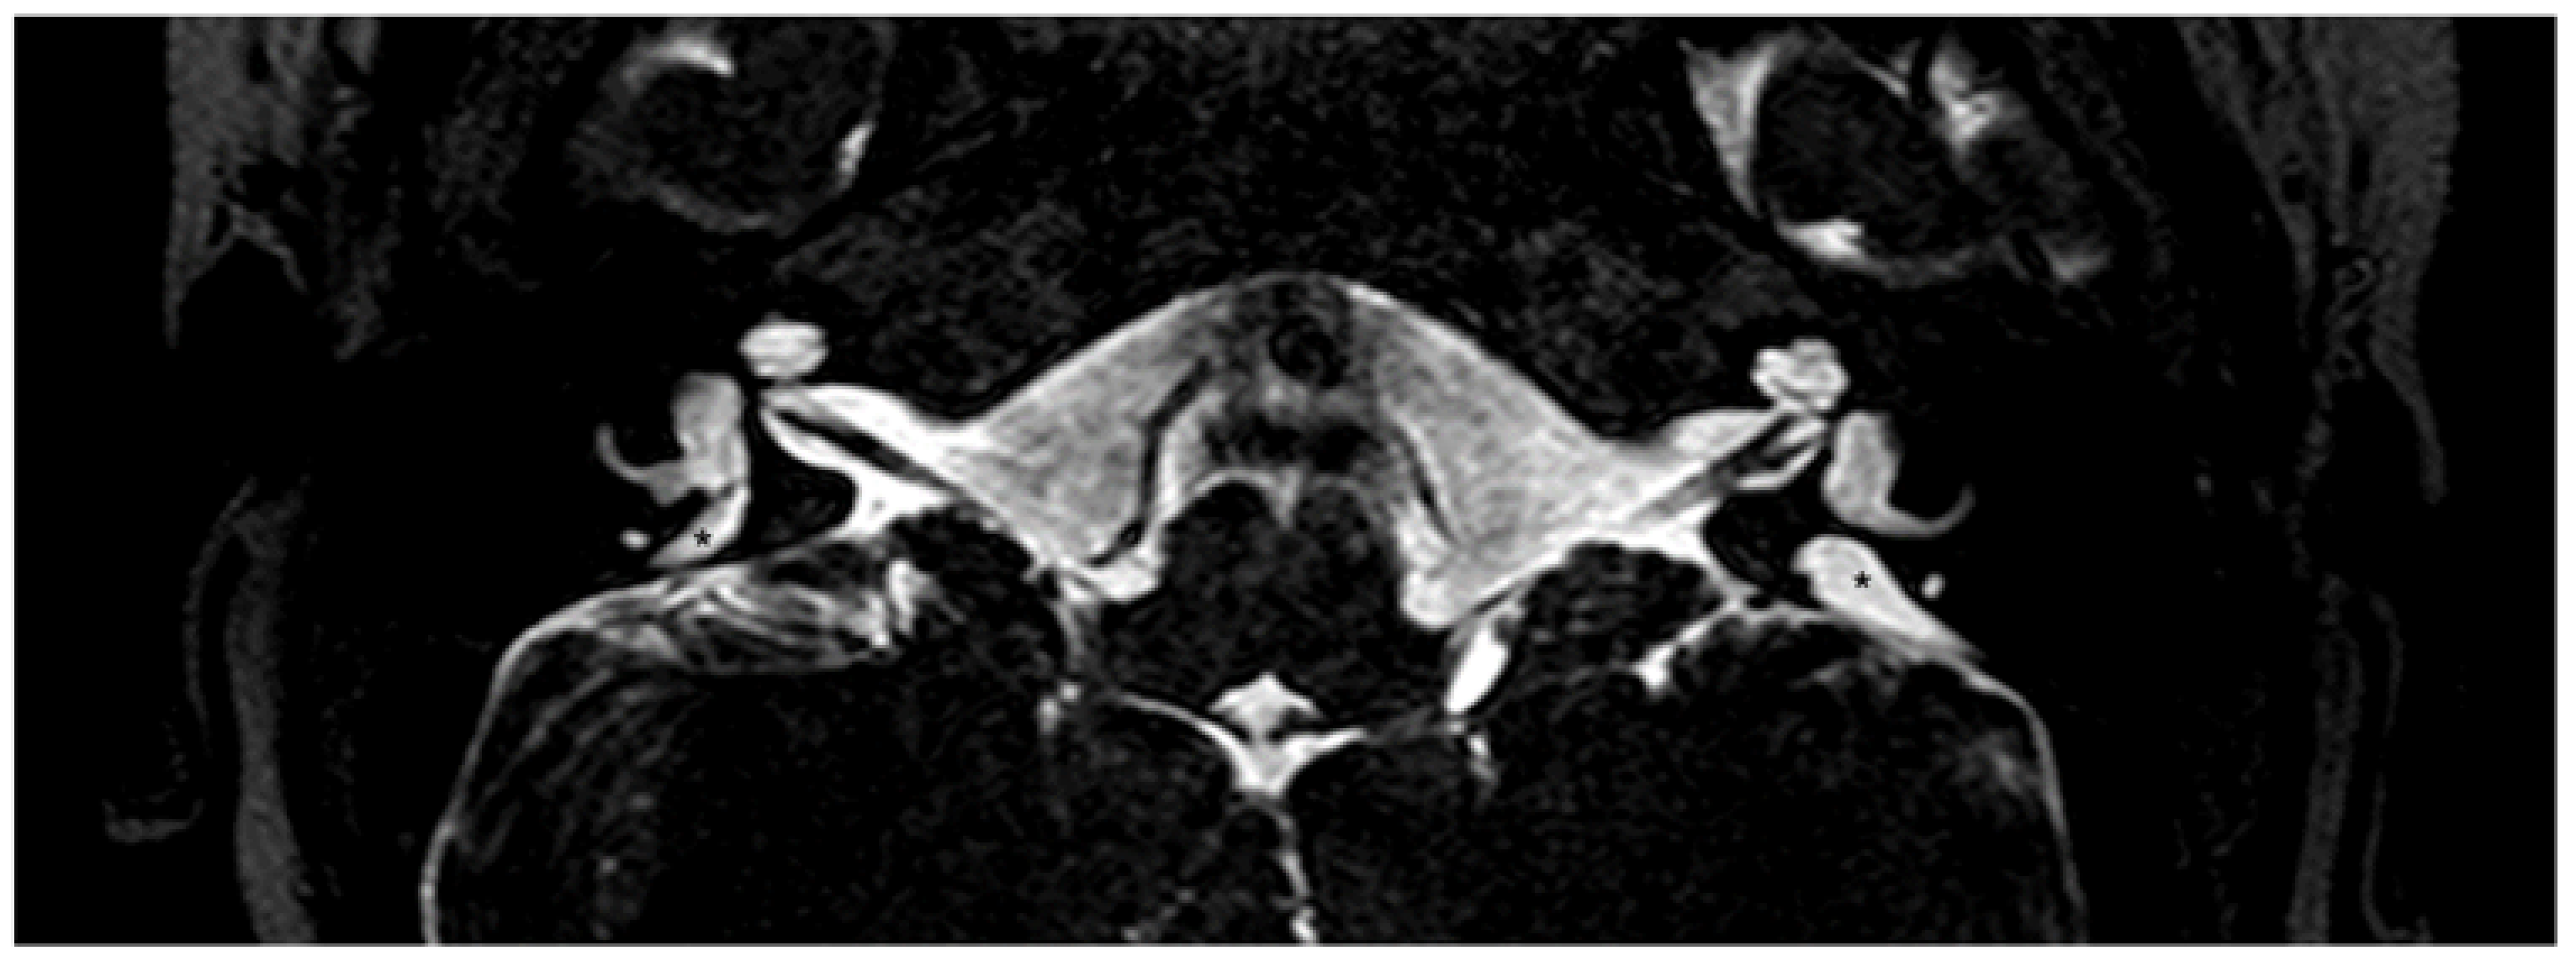

- Sone, M.; Yoshida, T.; Morimoto, K.; Teranishi, M.; Nakashima, T.; Naganawa, S. Endolymphatic hydrops in superior canal dehiscence and large vestibular aqueduct syndromes. Laryngoscope 2016, 126, 1446–1450. [Google Scholar] [CrossRef]

- Tsukada, K.; Usami, S.I. Detailed MR imaging assessment of endolymphatic hydrops in patients with SLC26A4 mutations. Auris Nasus Larynx 2020, 47, 958–964. [Google Scholar] [CrossRef]